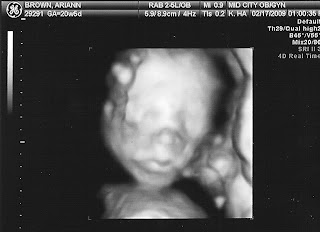

Had another ultrasound today to look at more development of the heart. They were very pleased at how things were progressing. Our sweet little girl, now at 20w and 5d, was already telling us who was in charge. She would move all over the place when we needed her to be still and wouldn't budge when we needed her to shift. She is growing like a weed. I can't believe how fast they change. We got a couple of 3D ultrasounds. She sure has huge lips. As you can see in one picture she is still pushing on my belly with her legs to make a little more room. After the ultrasound Mark and I went and looked at two daycares. One we liked and the other we probably wouldn't leave Cletus at. Anyway hopefully this process will end real soon. Hope everyone is doing well and we will keep up with the posts. See you all soon.